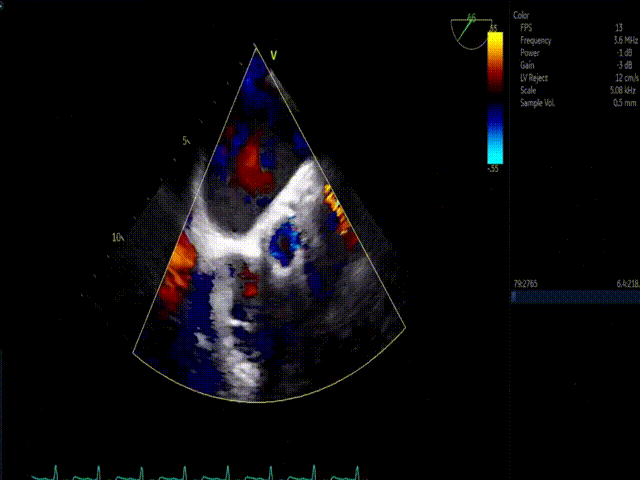

患者为77岁女性,三叶式主动脉瓣。术前超声心动图提示主动脉瓣重度狭窄伴轻度关闭不全、峰值流速 5.3m/s、平均跨瓣压差 63mmHg、有效瓣口面积 0.60cm²;左房内径增大,左心室舒张功能异常;二尖瓣轻度狭窄伴中-轻度关闭不全、三尖瓣轻度关闭不全;LVIDd:50mm,LVEF:63%。

考虑患者左冠开口偏低,左瓣叶冗余影响左冠血流,预置GuidezillaII支撑保护,之后采用TaurusAtlas 22mm球囊预扩张,植入AV26 TaurusNXT主动脉瓣,起搏140次/分频率下,在左右重合位瓣膜释放达到工作位,造影显示锚定位置理想,之后在右窦中心位下再次确认植入位置,同时超声评价瓣膜位置及血流动力学情况,最终0位精准释放瓣膜。无回收,无球囊后扩张,未植入冠脉支架。术后即刻超声心动图评估显示瓣膜位置良好,微量瓣周漏,主动脉瓣口峰值流速为1.80m/s,平均跨瓣压差为5mmHg,有效瓣口面积 2.4cm2,血流动力学指标理想。在线专家称赞陈绍良教授、张俊杰教授团队完美完成了一例高冠脉风险、重度主动脉瓣狭窄TAVI手术。

术中影像

1、预置LCA保护 ;2、主动脉根部造影;3、球囊预扩;4、瓣膜初始释放;5、瓣膜释放至工作位造影;6、瓣膜最终释放造影